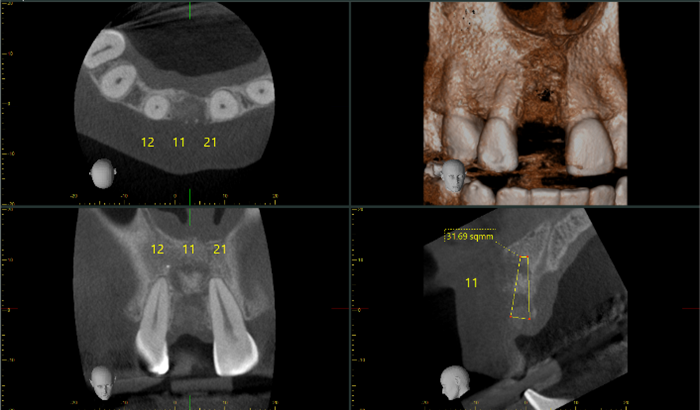

Paciente que presenta zona edéntula a nivel del 11 se le realiza tomografía, la cual podemos concluir que; zona sin diente con calidad de hueso tipo cuatro (Capa delgada de hueso cortical rodeando un núcleo de hueso trabecular de baja densidad). (Lekholm & Zarb). Reabsorción moderada a avanzada del reborde residual. Se realizan reconstrucciones tridimensionales y cortes multiplanares en 11, 12, 21, con mediciones en 11 (observar imagen anterior).